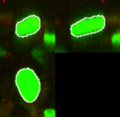

- In our recent work[1] on studying the variation of nuclear structure in tumor microenvironments [2], we have used SPHARM-PDM [3] to model 3D nuclear shape. We are interested in using itkQuadEdgeMesh as the mesh representation to this end and will be evaluating the use of this class for our system.

- Current system for statistical shape analysis of nuclear morphology uses [3] to generate the representation